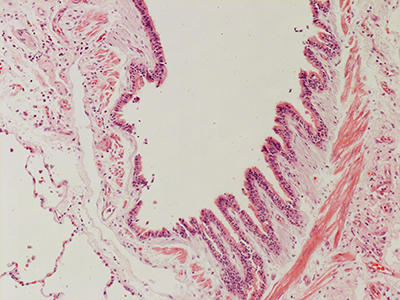

31 Year Old Adult Human Lung D003 H&E